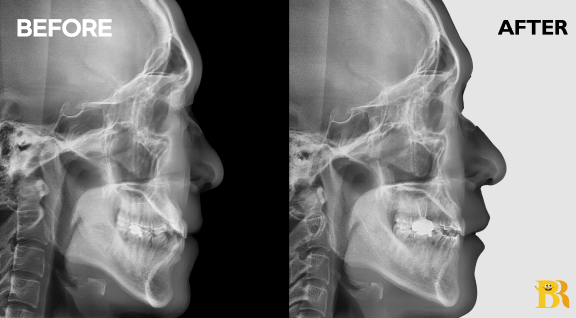

[치열불규칙이 심각한 수준의 케이스] 치아를 움직일 공간이 부족하였으나 측면 안모를 고려하여 비발치 교정으로 진행하였습니다

[상악 송곡니 덧니 및 앞니 중심선 불일치 케이스] 발치교정으로 가지런한 치열을 완성하면서 전체적인 외모를 안정적으로 유지시켰습니다

[전체적으로 불규칙한 치열 케이스] 발치하지 않고 교정치료를 진행 하여 치열 개선에 따라 옆모습도 좋아졌습니다